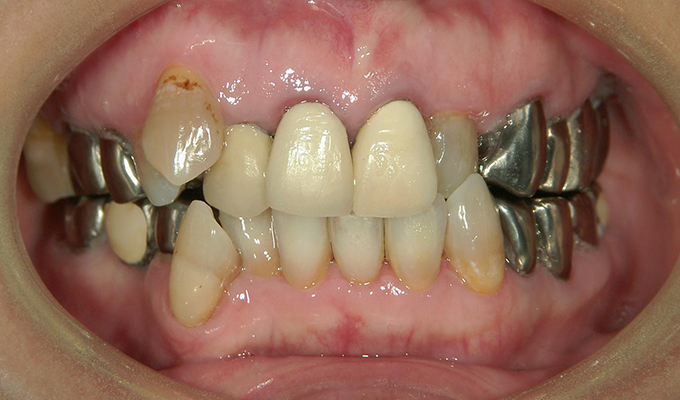

case5インプラント+メタルボンドブリッジ

初回メンテナンス時(2012年)

最新メンテナンス時(2023年)

- 40代女性 (2010年)

- 5年ほど前に上に総入れ歯を作った。(マグネットタイプ)食事してたら人口歯が取れてしまった。インプラントに興味がある。40代なので入れ歯はやっぱり嫌、とのことでした。

- 治療内容

- 上・・・虫歯の根だけの歯が数本残っているためすべて抜歯し仮義歯作成しました。最終的には8本インプラントを埋入し上部構造はメタルボンドです。

下・・・保存できる下の歯はメタルボンドブリッジにし、奥歯のない部分に3本インプラントを埋入しました。治療期間は2年ほどかかりましたがしっかり食事ができるようになったので嬉しいと、満足していただけました。

以降定期的にメンテナンスに来院いただき11年経過してもいい状態を維持されています。